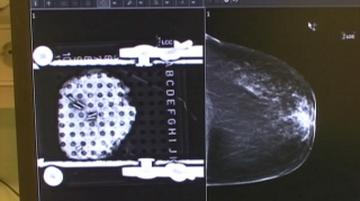

"Aparatura nam namreč omogoča povečano tridimenzionalno sliko, instrumenti pa so zelo natančni." Ob tem je za bolnike še kar nekaj prednosti - ne potrebujejo transfuzije, prav tako je bolečina blažja, zato jemljejo znatno manj analgetikov.